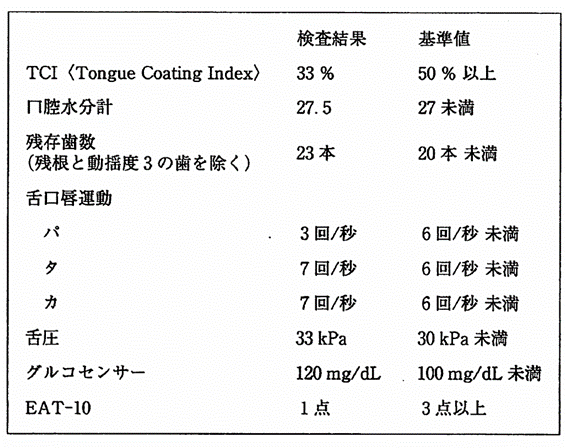

午前-78

28歳の女性。口臭を主訴として来院した。起床時に口臭を自覚することがあり、家族からも口の臭いを指摘されたという。検査結果を表に示す。医療面接で適切なのはどれか。2つ選べ。